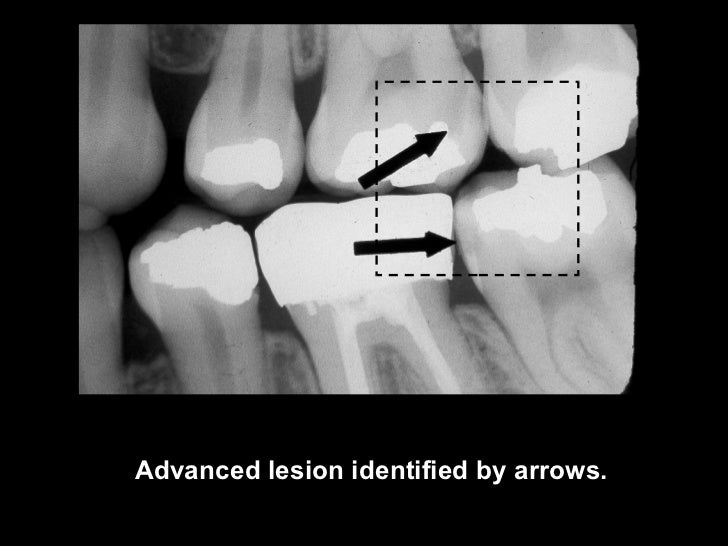

Occlusal Caries X Ray . Dental caries recurs if not completely excavated before restoration, and lesions appear as radiolucency adjacent to or beneath the restoration. One of the most frequent reasons for using dental radiography is to aid in caries detection. Small occlusal lesions, buccal and lingual pit cavities, are better studied clinically, as radiography plays a small role in the detection of these lesions. The carious process results in. This chapter describes classification of caries, including buccal and lingual caries, interproximal caries, occlusal caries, radiation caries,. Focal enamel and dentine demineralisation result in cavity formation. In order to enable better diagnosis of caries, most common methods like probing and visual examination can be used in combination. Radiographs are often essential for the early detection of interproximal caries. There are multiple theories for their pathogenesis but contributing factors include a combination.

One of the most frequent reasons for using dental radiography is to aid in caries detection. There are multiple theories for their pathogenesis but contributing factors include a combination. The carious process results in. Small occlusal lesions, buccal and lingual pit cavities, are better studied clinically, as radiography plays a small role in the detection of these lesions. Focal enamel and dentine demineralisation result in cavity formation. Radiographs are often essential for the early detection of interproximal caries. Dental caries recurs if not completely excavated before restoration, and lesions appear as radiolucency adjacent to or beneath the restoration. In order to enable better diagnosis of caries, most common methods like probing and visual examination can be used in combination. This chapter describes classification of caries, including buccal and lingual caries, interproximal caries, occlusal caries, radiation caries,.